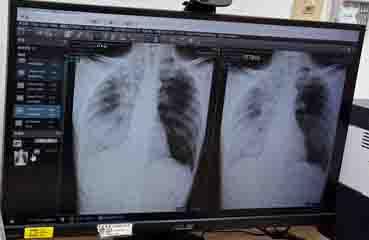

如果大家好奇我的肺炎有多嚴重的話,剛好有拍到X光。(降一下解析度,避免個資外洩)

右邊快全白了,這就是肺浸潤,沒處理好可是會被一波帶走的。其實住院要拍到這個很難,那是要剛好主治醫師出現在護理站,且正在看我的X光,然後我們剛好出現被叫住,直接在護理站解釋病情。不然一般都是主治醫師去病房講解而已,就沒機會拍到了。